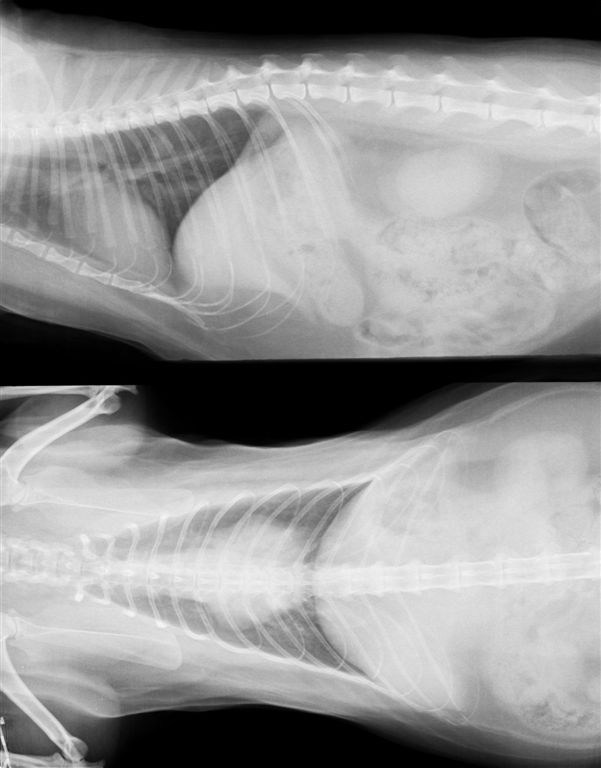

犬 13歳 乳腺腫瘍

肺にびまん性転移像がみられる。1年前に乳腺腫瘍の手術をうけ右側乳腺を切除したが、左側乳腺をそのままにしたため、拡大し現在腫瘍は8cmを超える。このような場合は手術などで体調が崩れると悪化が加速する場合が多い。